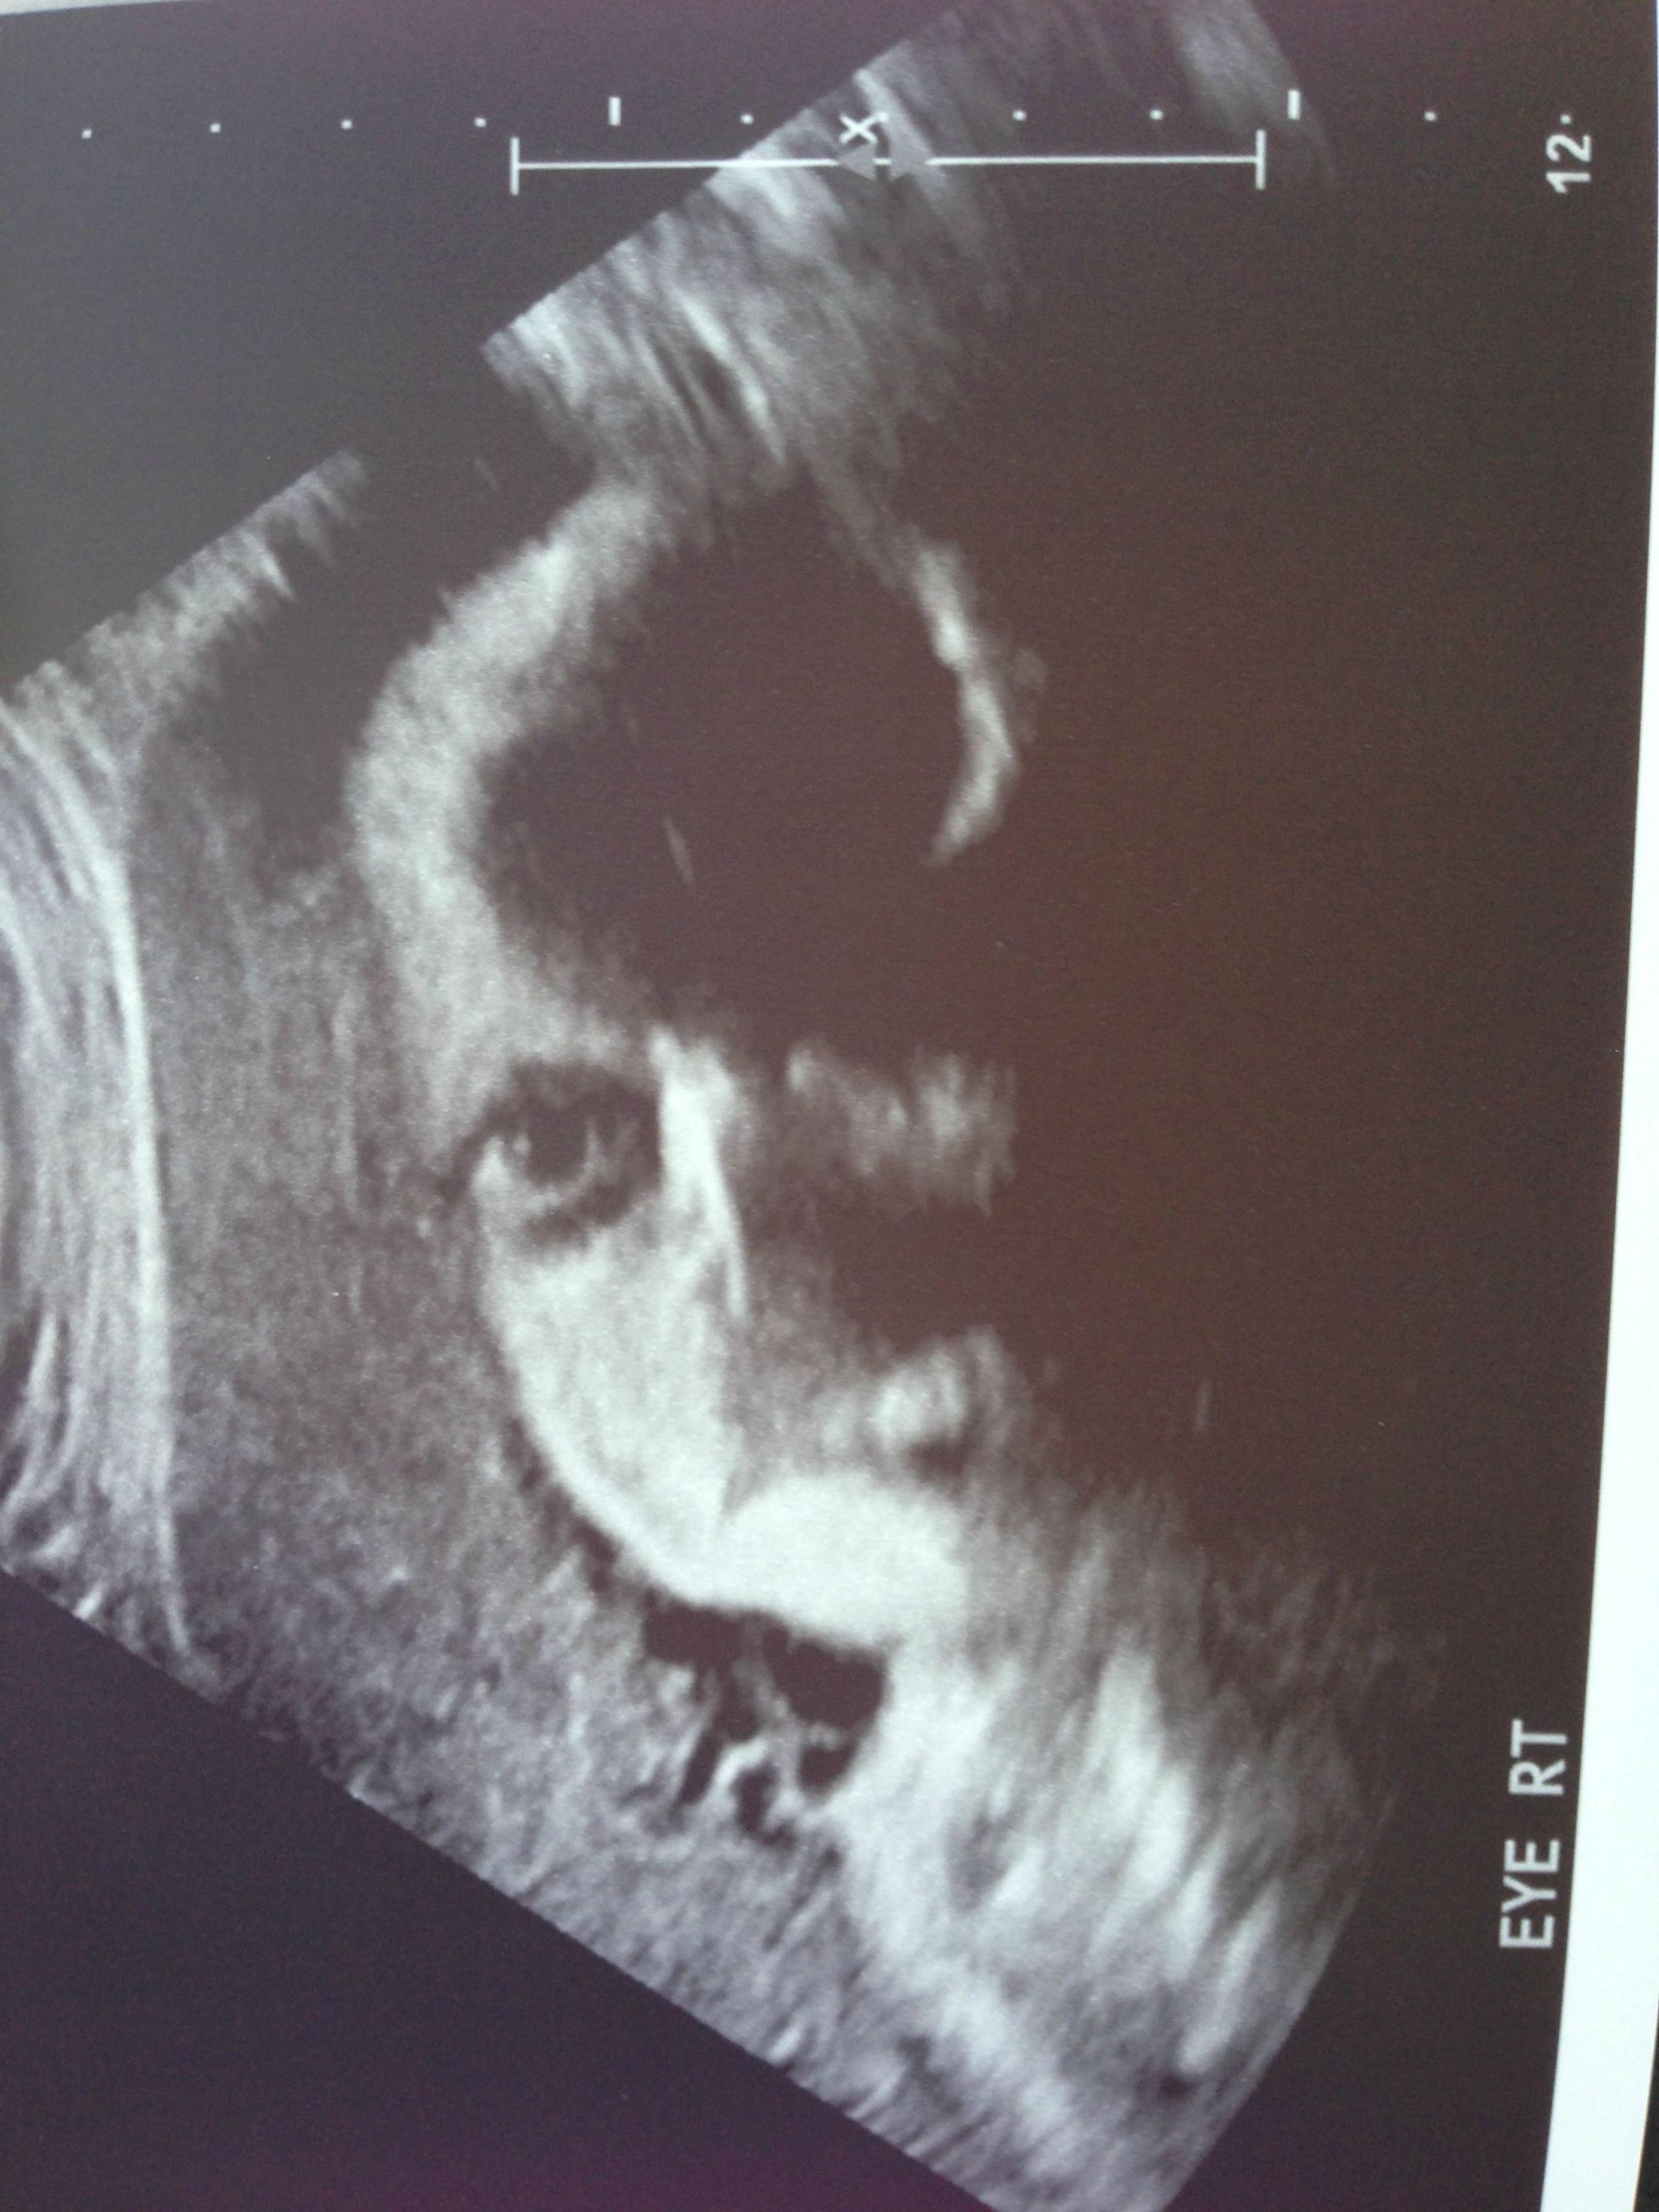

Sympa l’échographie…